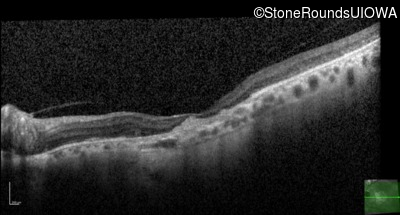

Optical Coherence Tomography - Right - 20/125 -2

Exemplar / OCT Stack

OCT Stack